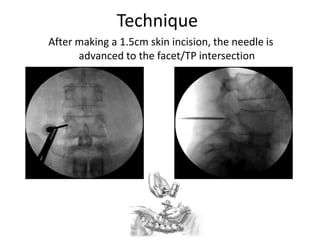

Technique

After making a 1.5cm skin incision, the needle is

advanced to the facet/TP intersection

AP Fluoroscopy is KEY

to safe pedicle

navigation. The critical

aspect relates to staying

lateral to the medial

wall. AP Fluoro is the

only view that gives

that information. A

good AP will also give

some sagital plane

information